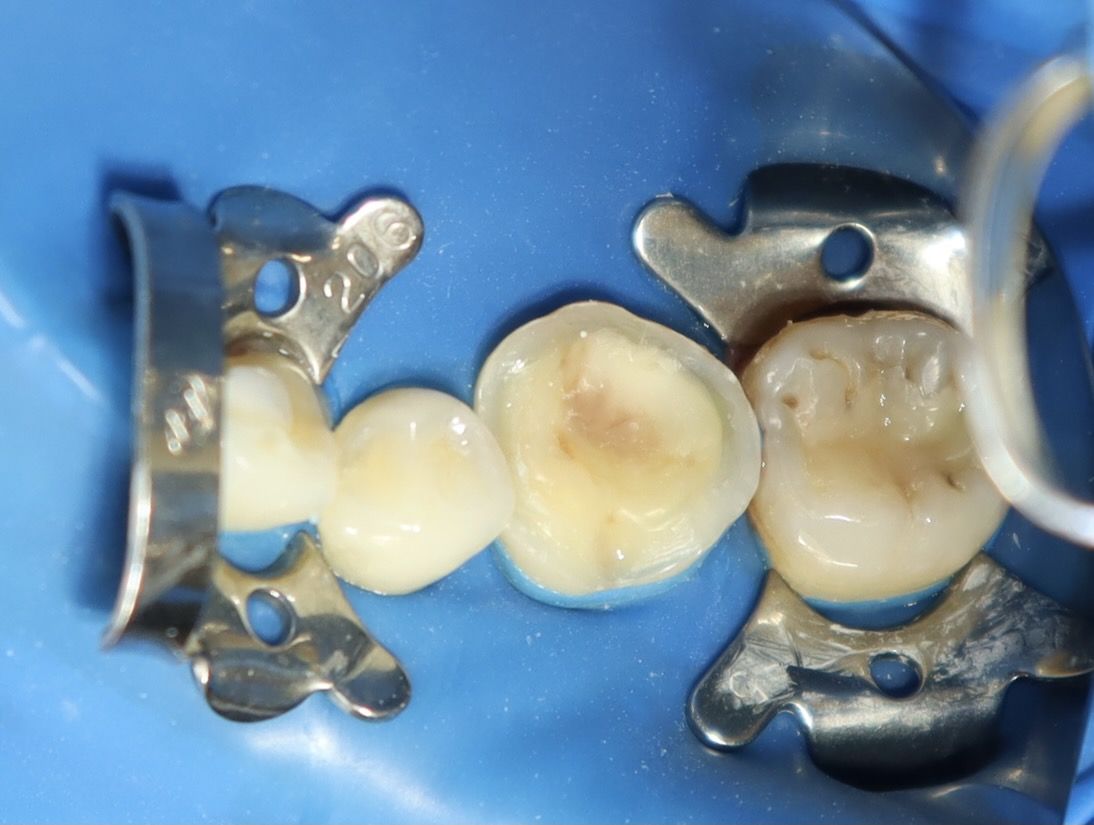

術中照片